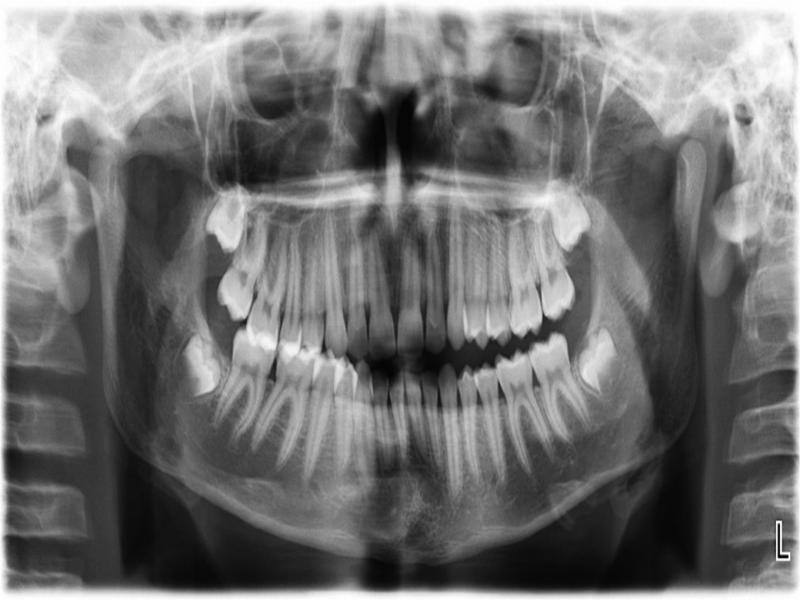

Figure 2.